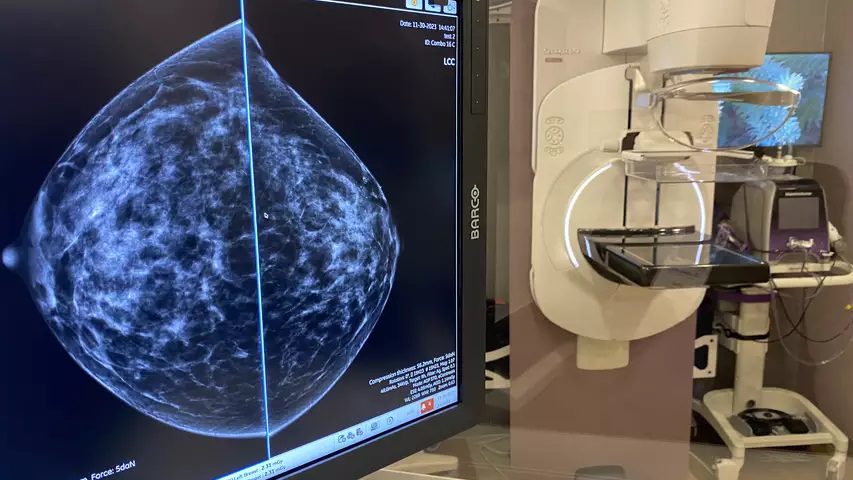

Merit Medical Systems Innovates Breast Cancer Care Technology

Merit Medical Systems has achieved FDA clearance for its groundbreaking SCOUT MD Surgical Guidance System, a significant advancement in breast cancer care. This innovative system enhances tumor localization with precise accuracy, reducing the need…